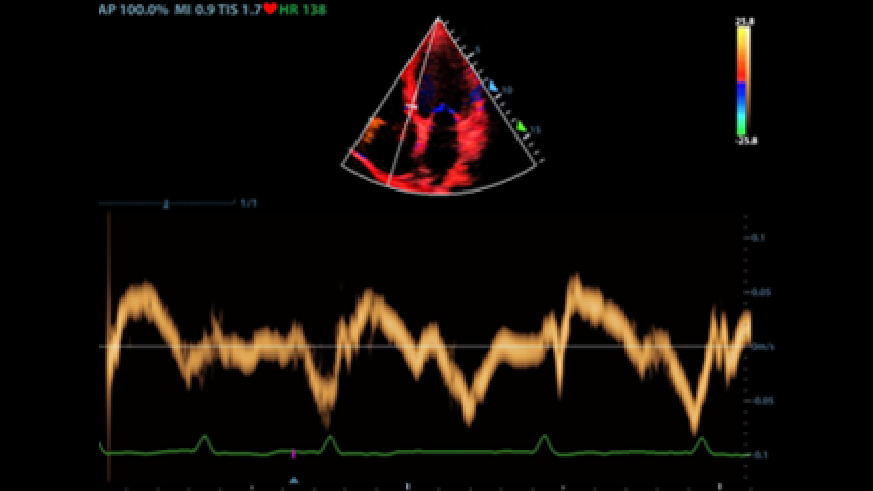

2Smart VTI

Automatische meting van de VTI (Velocity Time Integral ) en CO (Cardiac Output), voor een snelle beoordeling van de hartfunctie. Zoek automatisch het kleurvlak en de PW-samplelijn in realtime. Een grafiek met parametertrends over CO, SV en VTI om de besluitvorming te ondersteunen.

3Smart IVC

Automatische meting van IVC-parameters (Inferior Vena Cava) helpt bij de beoordeling van de volumestatus en begeleidt de vloeistoftherapie. Een grafiek van de parameterwijziging voor CI of DI en IVCV om veranderingen van ernstig zieke pati?nten te monitoren.